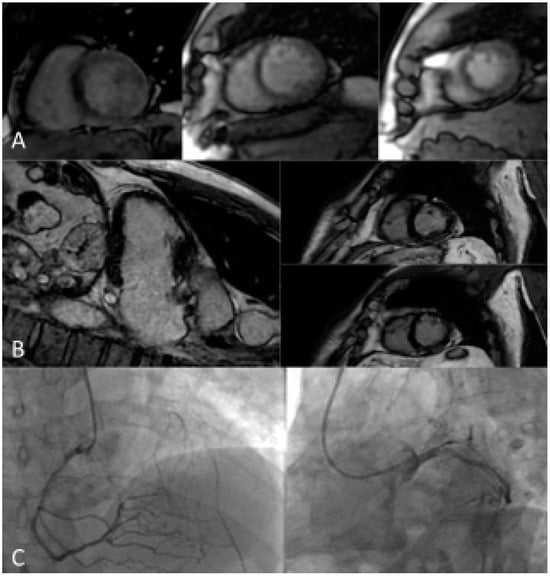

2.2.3. Stress Cardiac Magnetic Resonance Imaging